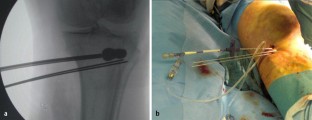

Abb. 3

Using the balloon technique achieves a precise and safe fracture reduction. This internal osteoplasty combines a minimal invasive percutaneous approach with a gently rise of the depressed area and the associated protection of the stratum regenerativum below the articular cartilage surface. This article lights up the surgical procedure using the balloon technique in tibia depression fractures.

This article reports on an innovative treatment concept to address split depression fractures (Schatzker type II) and depression fractures (Schatzker type III) of the tibial head using the balloon osteoplasty technique for fracture reduction.